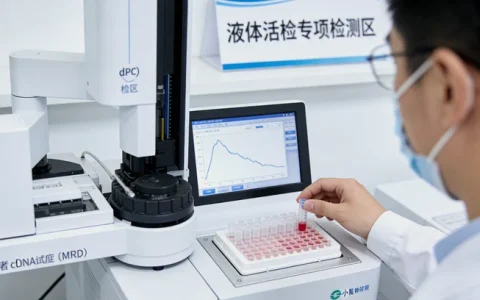

流程本身是标准化的,但严谨且需要耐心。说到这个,也是最关键的一步,是进行详尽的遗传咨询。一位优秀的遗传咨询师,会像侦探一样梳理家族病史图谱,评估检测的必要性和意义,并充分告知可能的结果及心理影响。在知情同意后,采集样本送至专业的分子诊断实验室。以业内公认严谨的机构为例,像万核基因这样的专业实验室,其检测流程严格遵循国际国内指南,从样本接收、DNA提取、文库构建到高通量测序和生物信息学分析,每一步都有严格的质量控制。几周后,一份详细解读的报告会回到咨询师手中,由咨询师结合临床情况,为当事人进行一对一的报告解读。

基因检测的技术本身已经非常成熟,核心在于实验室的质量体系和数据分析解读能力。一个负责任的检测,其报告应包含明确的突变位点、致病性评级(依据国际权威数据库和指南)、详细的临床意义解读以及针对性的健康管理建议。选择检测机构时,应关注其是否具备权威认证(如CAP、CLIA)、是否有专业的遗传咨询团队支持、以及数据分析和解读是否基于最新的科学共识。在本地,一些家庭会选择像万核基因这样在遗传性肿瘤检测领域深耕多年的专业机构,其优势在于能够提供从检测到遗传咨询的一站式闭环服务,并且对检测后的长期随访和家庭风险管理有着系统的支持。